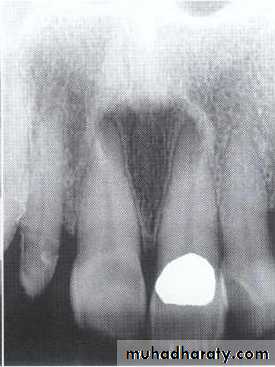

Traumatic cyst*Mandible > Maxilla. <20 years of age.

*Asymptomatic, expansile, associated with history of trauma. *Extend between the roots of teeth with scalloped border .

*Aspiration is not productive, empty cavity.